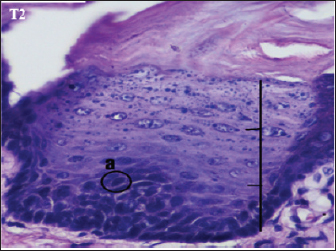

The histopathological appearance of the rat tongue epithelium in the T2 group showed irregular stratified cells. In the basal and parabasal layers, upwards to one-third of the thickness of the epithelium reveals differences in the form and size of cells and nuclei. Hyperchromatic nuclei were found in the epithelium’s basal and parabasal layers, which do not extend beyond the lowest one-third. The layers of spinosum and granulosum had no dysplastic cells (Fig. 4).

Fig. 4. Histopathological description of the rat tongue epithelium in the T2 group, microscope at ×400. (a) Variations in cell shape with hyperchromatic nuclei.

The T2 group showed cell improvement toward mild dysplasia. According to Speight (2007), mild dysplasia (grade I) indicates proliferation or hyperplasia of basal and parabasal layer cells that do not extend beyond the lower third of the epithelium, pleomorphism in cells or nuclei, and minimum tissue changes.